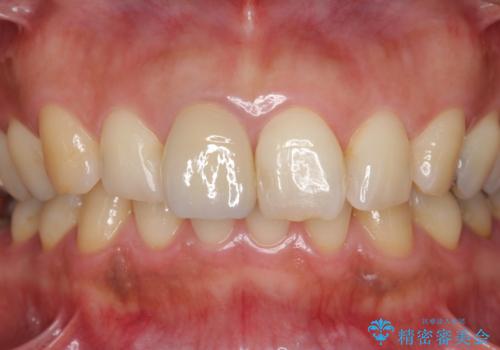

折れてしまった前歯 オールセラミックによる審美改善

- 13.2万円(ジルコニアクラウン・仮歯)費用は治療当時の料金となります

破折リスクを少なくするため前歯でかじったり硬いものを噛み切る等の行為は避けた方が良いとお伝えし、現状5年問題なく経過しています。